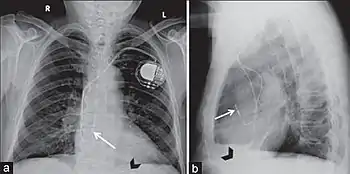

Permanent pacing with an implantable pacemaker involves transvenous placement of one or more pacing electrodes within a chamber, or chambers, of the heart, while the pacemaker is implanted under the skin below the clavicle. The procedure is performed by incision of a suitable vein into which the electrode lead is inserted and passed along the vein, through the valve of the heart, until positioned in the chamber. The procedure is facilitated by fluoroscopy which enables the physician to view the passage of the electrode lead. After satisfactory lodgement of the electrode is confirmed, the opposite end of the electrode lead is connected to the pacemaker generator.

A pacemaker may be implanted whilst a person is awake using local anesthetic to numb the skin with or without sedation, or asleep using a general anesthetic.[25] An antibiotic is usually given to reduce the risk of infection.[25] Pacemakers are generally implanted in the front of the chest in the region of the left or right shoulder. The skin is prepared by clipping or shaving any hair over the implant site before cleaning the skin with a disinfectant such as chlorhexidine. An incision is made below the collar bone and a space or pocket is created under the skin to house the pacemaker generator. This pocket is usually created just above the pectoralis major muscle (prepectoral), but in some cases the device may be inserted beneath the muscle (submuscular).[26] The lead or leads are fed into the heart through a large vein guided by X-ray imaging (fluoroscopy). The tips of the leads may be positioned within the right ventricle, the right atrium, or the coronary sinus, depending on the type of pacemaker required.[25] Surgery is typically completed within 30 to 90 minutes. Following implantation, the surgical wound should be kept clean and dry until it has healed. Some movements of the shoulder within a few weeks of insertion carry a risk of dislodging the pacemaker leads.[25]